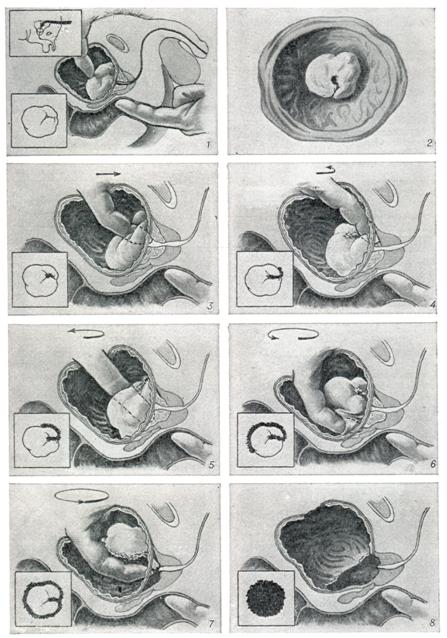

III стадия — стадия неполной хронической задержки мочи. Переход II стадии в III может проходить малозаметно для больного, но объективно всегда выражается наличием остаточной мочи, количество которой неуклонно нарастает. В III стадии заболевания страдают все вышележащие органы мочевого аппарата: тонус детрузора ослабевает, гипертрофия сменяется истончением стенки пузыря, мышечные волокна растягиваются и появляются многочисленные мелкие ложные дивертикулы. Особенно быстро наступает декомпенсация стенки пузыря при увеличении так называемой средней доли железы, которая как бы перекрывает путь к выделению мочи (рис. 3). Растущая вверх и кзади аденома предстательной железы крючкообразно приподнимает и сдавливает юкставезикальные отделы мочеточников, что хорошо видно (симптом «рыболовного крючка») на экскреторной урограмме. Недостаточное опорожнение мочевого пузыря приводит к расширению мочеточников и почечной лоханки; почечные сосочки уплощаются, почечная паренхима истончается от давления, что приводит к тяжелым нарушениям функции почек, исходом чего может явиться уремия. Вначале почка утрачивает способность концентрировать мочу и ей необходимо для выделения шлаков большое количество жидкости, позднее страдает способность разведения. III стадия длится годами; явления растяжения нарастают так медленно, что больной свыкается со своим состоянием, не ощущая увеличивающегося количества остаточной мочи. Это объясняется тем, что вместе с уменьшением сократительной способности пузыря снижается его чувствительность. Постепенно пузырь растягивается и может содержать 1,5—2 л мочи; напряжение скопившейся в мочевом пузыре мочи преодолевает сопротивление сфинктеров, и моча начинает непроизвольно выделяться по каплям. Заболевание переходит в следующую стадию.

Применяют экскреторную урографию, цистографию и уретроцистографию; наиболее рациональна лакунарная уретроцистограмма по Кнайзе и Шоберу (рис. 4). Кислород, введенный по катетеру в количестве 150—200 мл, растягивает мочевой пузырь в виде купола. Введенное вслед за кислородом жидкое контрастное вещество (20% раствор сергозина в количестве 20 мл) располагается в области дна мочевого пузыря, выявляя внутрипузырный рост аденомы предстательной железы. Этим методом определяют ряд типичных рентгенологических симптомов: «берета» (рис. 5), удлинения мочеиспускательного канала (рис. 6), «клинка сабли» (рис. 7), приподнятого дна.

Экскреторная урография, помимо определения функции почек, указывает на состояние нижних отрезков мочеточников, которые крючкообразно приподнимаются кверху, давая изображение «рыболовного крючка» (рис. 8). Рентгенологическое исследование выявляет также сопутствующие заболеванию камни и дивертикулы.

Эндоскопические методы исследования — цистоскопию, уретроскопию (см.) — следует проводить только при гематурии, подозрении на опухоль мочевого пузыря или для дифференциальной диагностики в неясных случаях. Уретроскопия показана в ранней стадии заболевания и не у пожилых, больных. При цистоскопии выявляются выбухания переходной складки в виде занавески (рис. 9), определяется средняя доля в виде барьера, уточняется наличие камней и сопутствующих заболеваний — цистита, язвы, папилломы. Во II и III стадиях заболевания цистоскопия затруднительна, может быть причиной развития инфекции, возникновения простатита и эпидидимита. Поэтому в последние годы большинство урологов предпочитает проводить цистоскопию в операционной перед операцией.